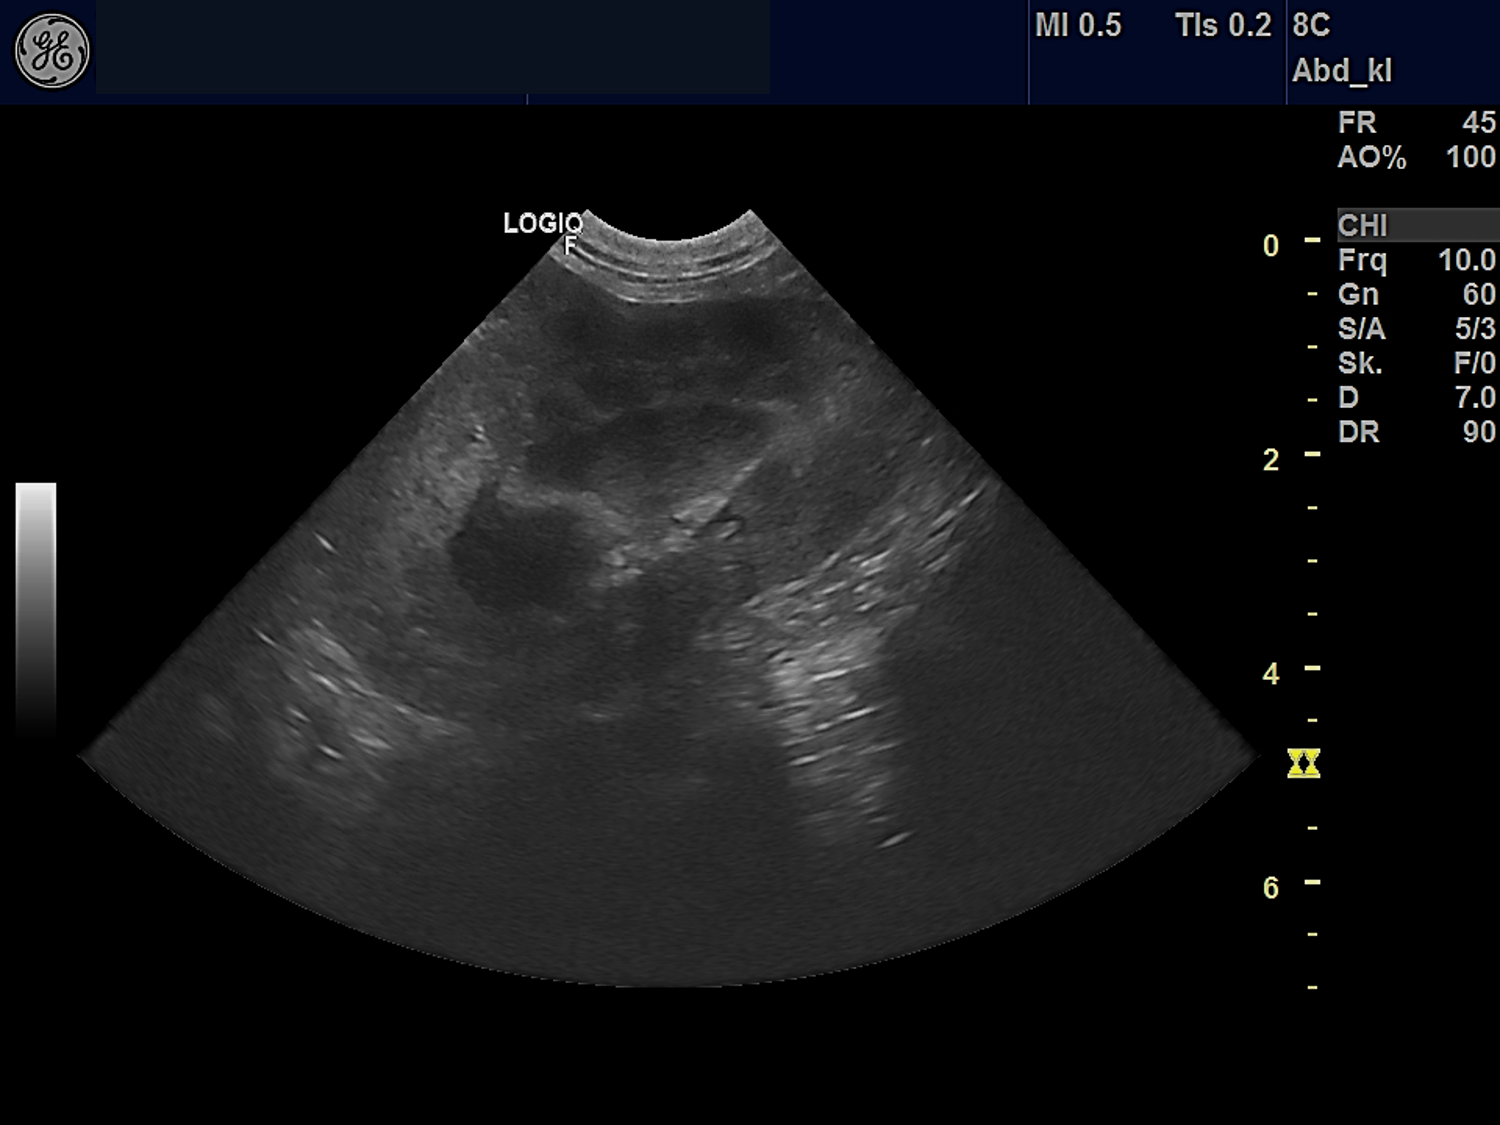

Zwei Monate später wurde Ela in meiner Praxis als Notfall vorgestellt. Die dauerhaften sommerlichen Temperaturen führten zu einem Kreislaufzusammenbruch. Die Hündin war deutlich ausgetrocknet und apathisch. Die Besitzerin erzählte mir von Ela und ihrer Krankenvorgeschichte. Um nun einen genaueren Einblick in Elas Nierenfunktion zu erhalten, besprachen wir gemeinsam die weitere Vorgehensweise. In der Praxis untersuchten wir den Urin von Ela. Es folgten weitere Blutuntersuchungen und eine Ultraschalluntersuchung der Nieren. Dabei stellten wir fest, dass Elas Nieren zu mehr als 70% geschädigt waren.